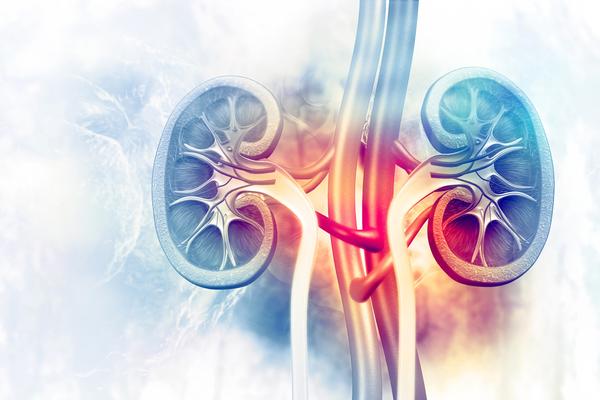

In Ayurveda, kidney disorders are associated with ...